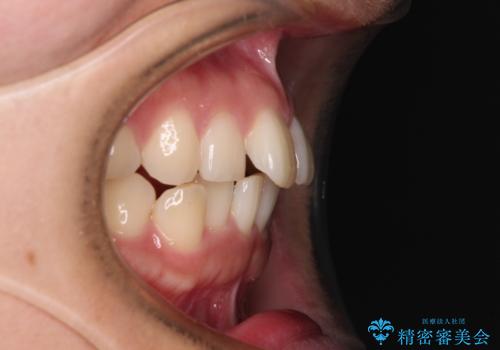

- 上下前歯のデコボコを気にして来院された患者様です。

ワイヤー矯正でもインビザラインでも、どの装置でも対応可能でしたが、安価で楽して素早く治療を終えたいとのことで、メタルブラケット装置による矯正治療を行うこととしました。